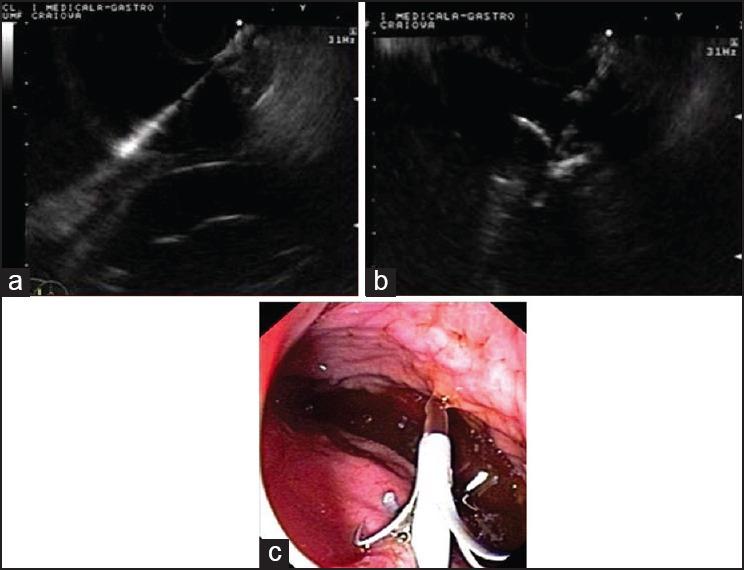

Pancreatic pseudocysts are fluid collections in the peripancreatic tissues associated with acute or chronic pancreatitis. Endoscopic ultrasound (EUS)-guided drainage has become an established indication, having better results as compared to percutaneous drainage, nonguided endoscopic drainage, or surgical drainage. The aim of this review is to assess critically the current literature concerning EUS-guided pseudocyst drainage and to review the place of the procedure in the clinical decision management algorithms of these patients.